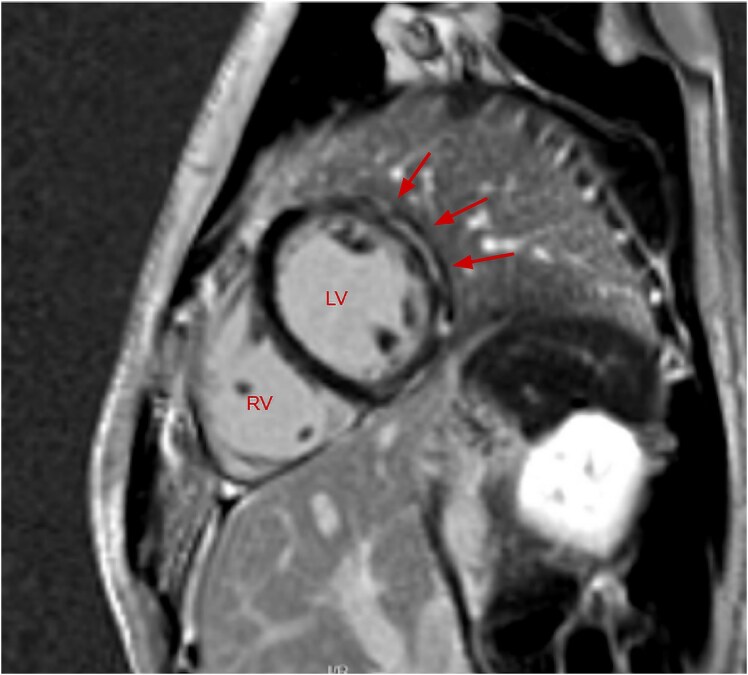

Case summary: A 17-year-old gentleman with a background history of developmental delay, gastrointestinal motility issues, retractile testes, and patellar dislocation presented to our emergency department with chest pain. Investigations revealed static mildly elevated troponin T. An electrocardiogram and transthoracic echocardiogram were both unremarkable. CMR revealed sub-endocardial and mid-wall LGE. He was treated as myocarditis with steroids and colchicine, however symptoms persisted and repeat CMR reported progressive LGE. The diagnosis of myocarditis was reconsidered given an atypical presentation and taking into account his past medical history, and so a whole gene exome was performed. This revealed a dual diagnosis of Klinefelter's Syndrome and a mutation in the dystrophin gene located on the X chromosome.